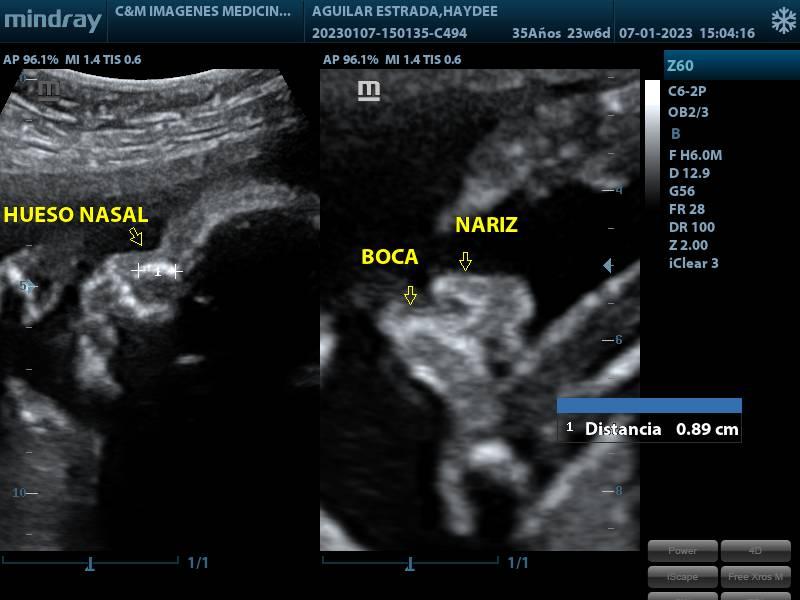

SCREENING DEL SEGUNDO TRIMESTRE

SERVICIOSCREENING DEL SEGUNDO TRIMESTRE

CONDICIÓNINDICACIONES: SE REALIZA ENTRE LAS 20 Y 24 SEMANAS DE GESTACION.

ESPECIFICACIONESSE ESTUDIA: BIOMETRIA FETAL DIAMETRO BIPARIETAL (DBP) CIRCUNFERENCIA CEFALICA (CC) CIRCUNFERENCIA ABDOMINAL (CA) LONGITUD DE FEMUR (LF) LONGITUD HUMERO (LH) SITUACION Y POSICION FETAL UBICACIÓN Y MADUREZ DE PLACENTA CANTIDAD DE LIQUIDO AMNIOTICO (ILA) SEMANAS DE GESTACION PESO FETAL SEXO FRECUENCIA CARDIACA FETAL (LCF) OBSERVACION MOVIIENTO FETAL ESTUDIO ANATOMICO FETAL ESTOMAGO, PULMONES, VEJIGA, RIÑONES EVALUACION DIAFRAGMA ESTUDIO CORAZON (4 CAMARAS CARDIACAS, VALVULAS, FLUJO SANGUINEO) CABEZA FETAL (CEREBELO, CSP, VENTRICULOS LATERALES, CISTERNA MAGNA, FOSA POSTERIOR, ETC) CARA FETAL (ORBITAS OCULARES, CRISTALINO, HUESO NASAL, LABIOS, NARIZ OBSERVACION COLUMNA VERTEBRAL Y EXTREMIDADES FLUJOMETRIA DOPPLER ARTERIAS UTERINAS (PREVENTOR PREECLAMPSIA) ARTERIA CEREBRAL MEDIA (ACM) ARTERIA UMBILICAL RELACION CEREBROPLACENTARIA.